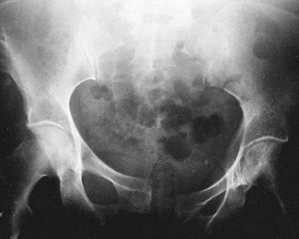

Figure 28.7.

Fixation of the left sacroiliac joint with the Terray sacroiliac joint plate and fixation of the symphysis with one plate superiorly and a bone graft fixed anteriorly with two screws. The L-5 nerve root deficit improved dramatically immediately after surgery. |